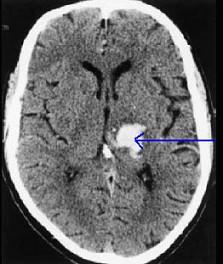

问题 患者,69岁,既往有高血压病史5年,因突发头痛,右侧肢体无力1天入院,行头颅CT扫描如图所示,可诊断为()

选项 A.左壳核出血 B.左颞叶出血 C.左尾状核 D.左丘脑出血 E.右丘脑出血

答案 D